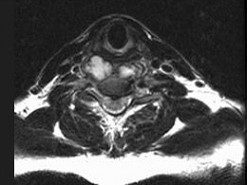

男,41岁,颈痛,发热,请结合图像,选出最可能的诊断()

A.化脓性脊柱炎

B.脊柱转移瘤

C.椎体压缩骨折

D.脊椎结核

E.椎间盘突出